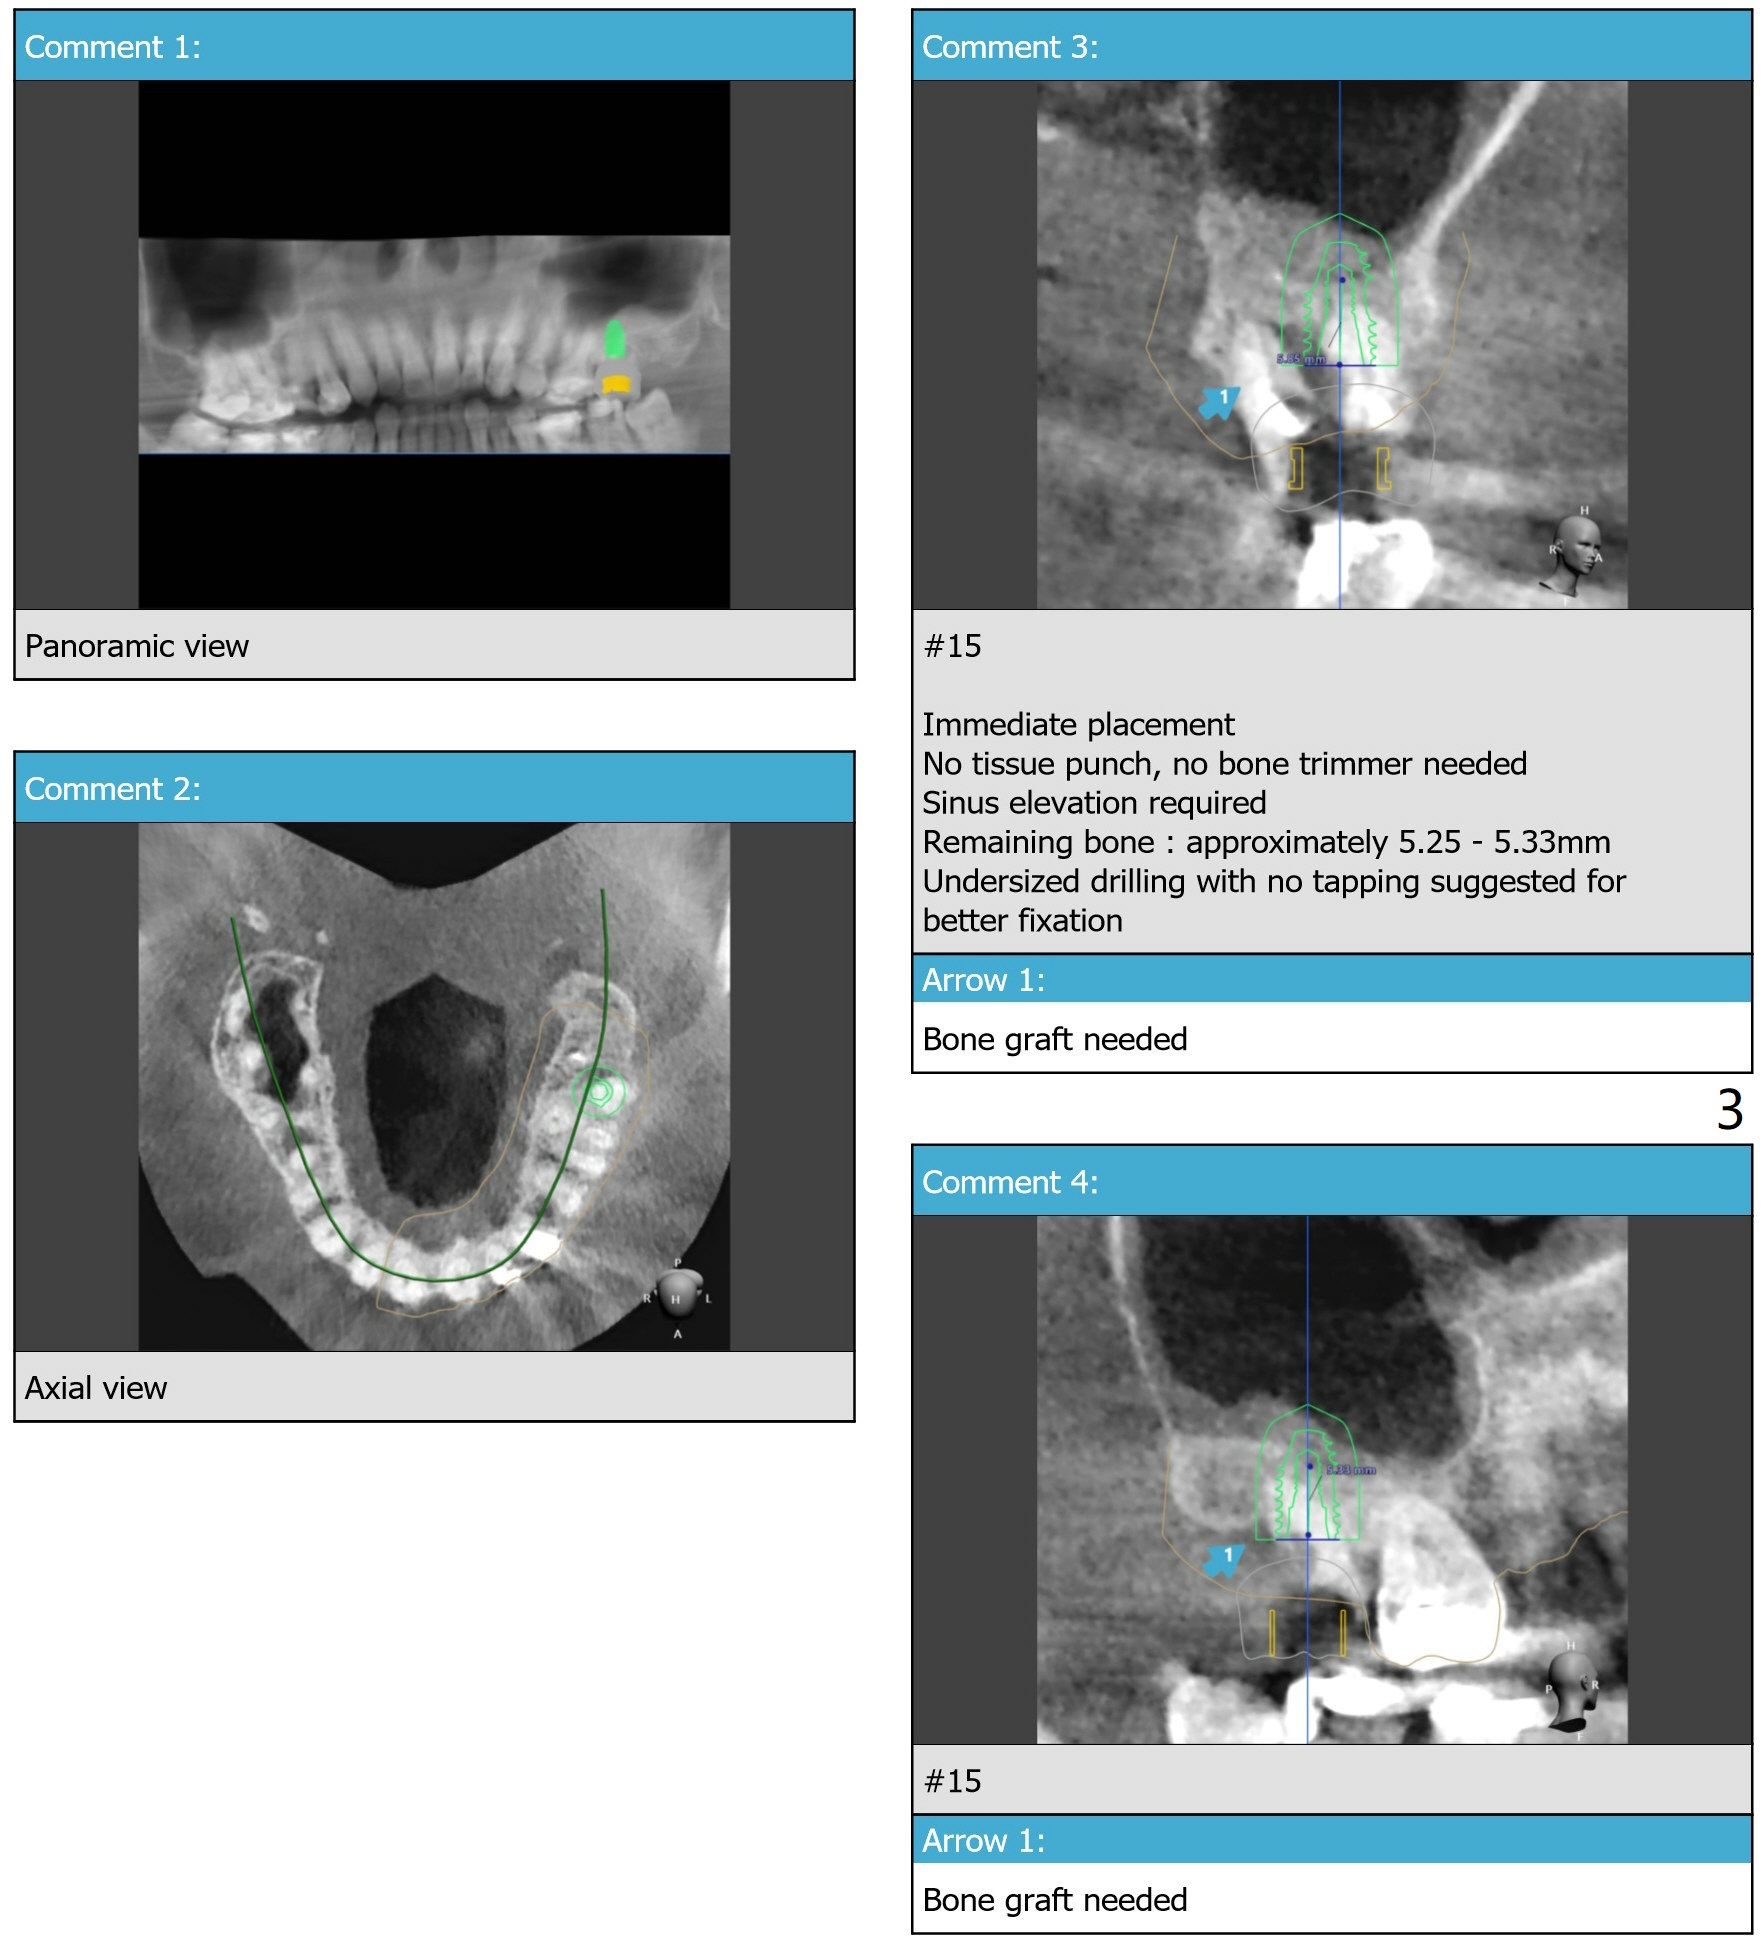

Return to Upper Molar Immediate Implant, Trajectory II

Xin Wei, DDS, PhD, MS 1st edition 10/03/2019, last revision 11/06/2019